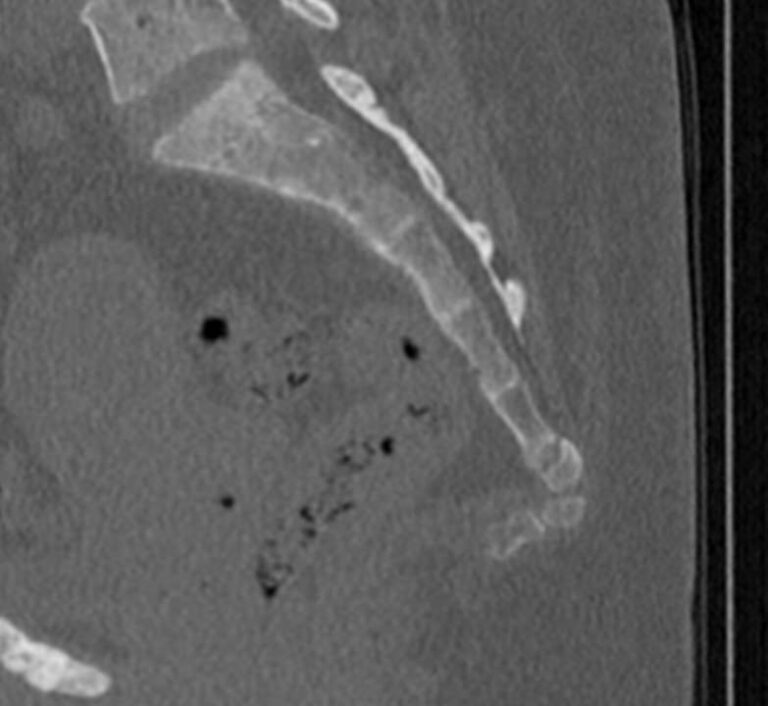

Одним из наиболее информативных методов диагностики заболеваний копчика является мультиспиральная компьютерная томография. Метод основан на использовании рентгеновского излучения и применения инновационных компьютерных программ для детальной визуализации состояния органов и систем организма. Процедура отличается быстротой, безболезненностью и неинвазивностью (то есть проводится без нарушения целостности кожи и расположенных под ней тканей).

В наших центрах обследование копчика выполняется на современных мультиспиральных томографах TOSHIBA AQUILION, оснащенных увеличенным количеством сверхчувствительных детекторов, позволяющих производить 64 или 128 срезов с минимальной толщиной от 0,5 мм.

Инновационные возможности аппаратов дают возможность получить множество послойных снимков высокого качества и реконструировать на их основе трехмерную модель органа. Кроме того, аппаратура позволяет за счет сокращения времени сканирования максимально уменьшить лучевую нагрузку на пациента.

Что покажет КТ копчика

- перелом крестца или копчика, смещение позвонков и другие травмы, в том числе застарелые.

- кисты копчика.

- дегенеративно-дистрофические патологии позвоночника – остеохондроз и другие.